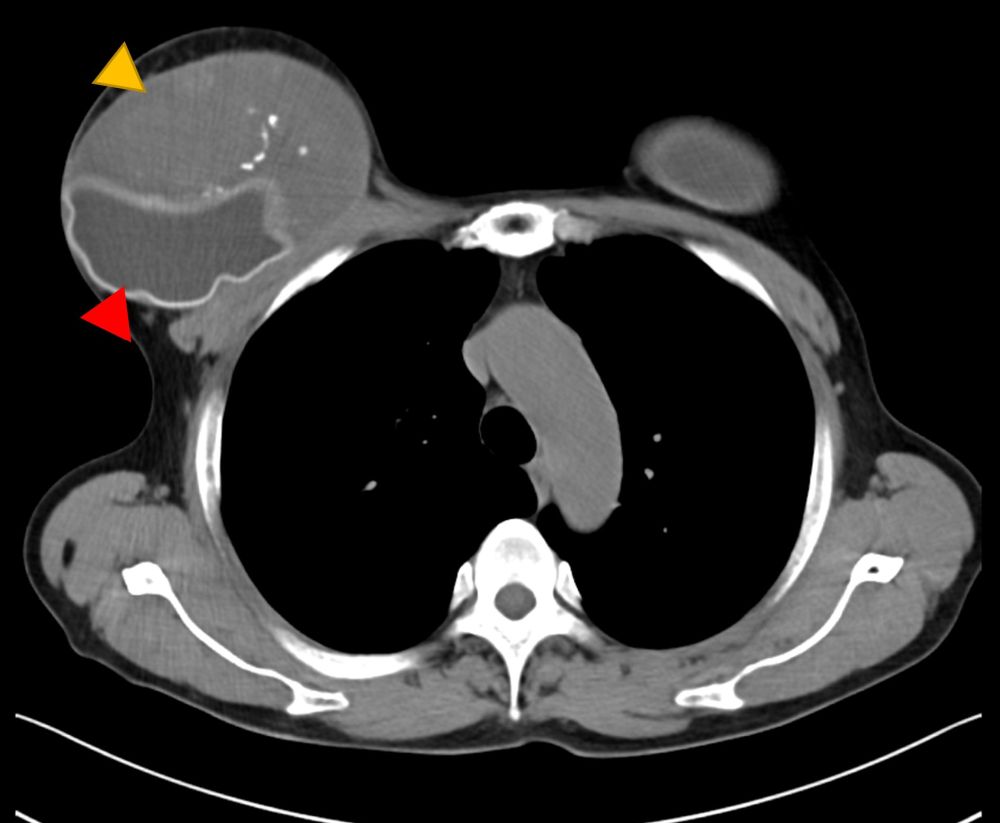

A 56-year-old Japanese transgender individual identifying as a woman had bilateral textured SBI inserted 25 years previously by a cosmetic surgeon for feminizing breast augmentation. She had undergone male to female sex reassignment surgery 12 years before the current presentation. She had taken hormonal drugs for about 5 years in her thirties. She took no oral medications such as anticoagulants or hormonal drugs after age 40. Two years prior to her visit to our department, her right breast became swollen without any specific cause. Redness and pain were observed 2 months prior to her visit. We observed redness, swelling, and abnormal morphology of the right breast (Figure 1). Blood tests showed no elevated inflammatory response or tumor marker or coagulation system abnormality (WBC 5,030/µl, CRP 0.11 mg/dL, PT-INR 0.9, APTT 30.6 seconds, IL-2 657). Computed tomography (CT) image showed a mass had formed under the ruptured SBI, and positron emission tomography (PET/CT) image showed swelling of the right axillary lymph node (Figures 2 and 3). Ultrasound-guided aspiration of fluid was performed and cytologically examined. However, flow cytometry showed no significant findings with few lymphocytes, and Giemsa banding could not be performed with little cell counts. Mammotome biopsy suggested a diagnosis of hematoma, but the possibility of breast implant–associated anaplastic large cell lymphoma (BIA-ALCL) could not be ruled out. The SBI ruptured just before surgery, so the mass and the axillary lymph node were surgically removed (Figure 4). Pathologic examination of the excised specimen revealed only hematoma formation and inflammatory granulation. At follow-up at 6 months postoperatively, there was no reformation of hematoma (Figure 5).

Figure 2. Computed tomography findings. Yellow arrow indicates the hematoma, red indicates the ruptured silicone breast implant.